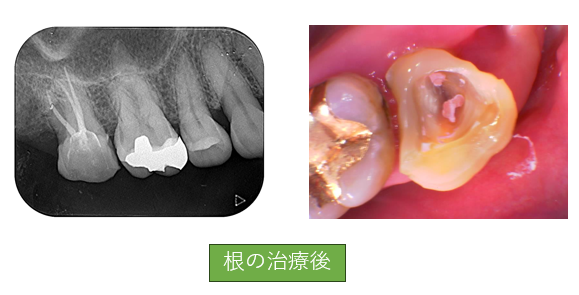

虫歯がかなり大きい場合は歯の神経をとる治療が必要となります。レントゲン写真でみると一番左の歯に白い筋のようなものが見えると思いますがこれは歯の神経をとったあとに粘土のような材料を詰めて細菌が溜まらないようにしています。この治療が大変で歯医者さんがやりたくない治療上位に君臨します。そしてこの治療が虫歯の治療すべての中で一番重要になります。

④土台を立てて被せ物をして完成

ここまでやって治療終了になります。今回の被せ物は自由診療になるためきれいなセラミックが入っていますが保険診療の場合は銀歯またはプラスチックの被せ物になります。